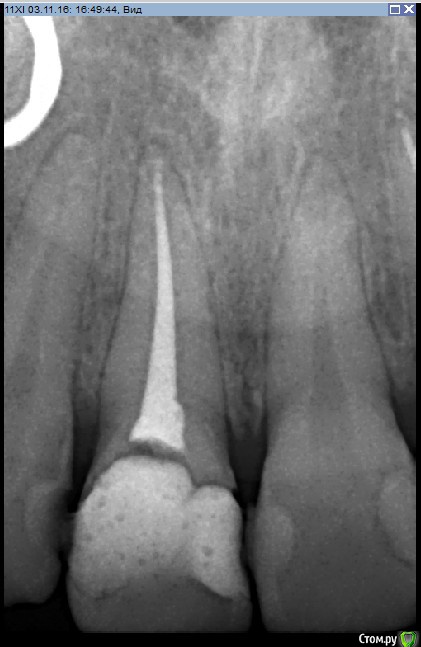

Рустам Опубликовано 4 ноября, 2016 Поделиться Опубликовано 4 ноября, 2016 Добрый вечер коллеги! Вчера обратилась пациентка (19 лет) с жалобой на подвижность коронки 1.1 зуба.Коронку убрал, скол достаточно глубоко (2-3мм ниже уровня десны), в зоне БШ. Удлинение во фронте не вариант на мой взгляд. Феррул не получить. Имплантолог ввиду возраста в имплантации отказывает.Пока сделал временный зуб на униметрике. КТ пока не делали. Записал на повторную консультацию. Как бы вы поступили в данной ситуации Ссылка на комментарий

Паращук Роман Опубликовано 7 ноября, 2016 Поделиться Опубликовано 7 ноября, 2016 (изменено) У вас хороший вариант экструзии и коронки до возможности имплантироваться или пока не отвалиться.У меня был схожий случай,потяжелее правда,но увы родители не вняли и ушли (с времянкой на беззольнике) к коллегам. Там ему поставили вкв и тянут зуб. С вашего позволения покажу. Парню 16 лет,повторный удар.http://s018.radikal.ru/i524/1611/c4/7349c2ca709a.jpghttp://s019.radikal.ru/i627/1611/b9/2e30c136cfca.jpghttp://i013.radikal.ru/1611/10/01fc91a62e4c.jpghttp://s014.radikal.ru/i328/1611/85/8c2938c163a1.jpghttp://s017.radikal.ru/i442/1611/dd/fbc284b9687d.jpg Изменено 7 ноября, 2016 пользователем Паращук Роман 4 Ссылка на комментарий